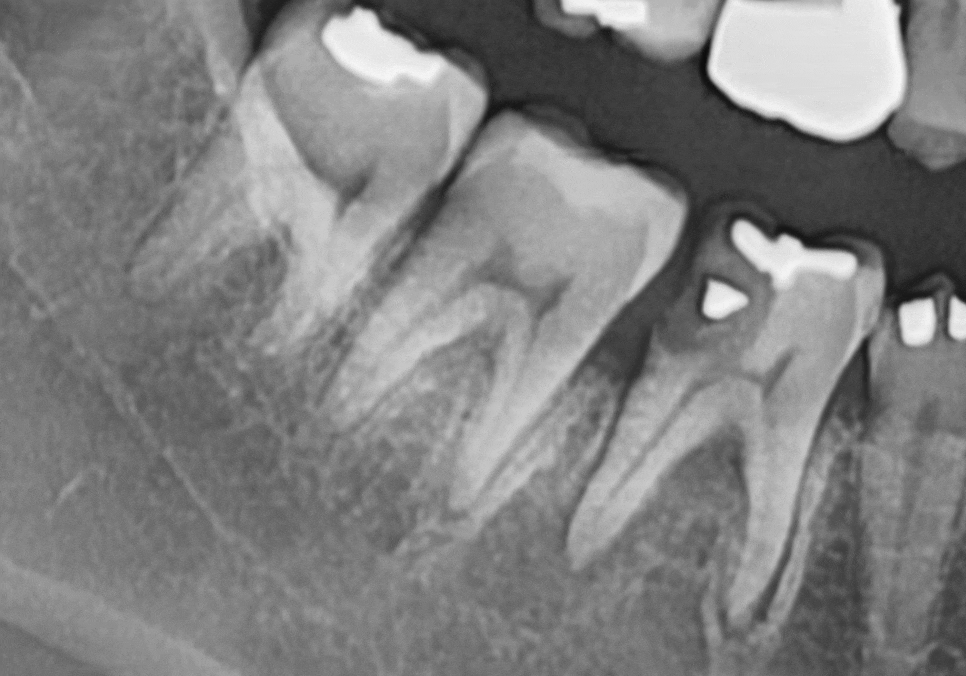

여기에 더해 바로 뒤쪽 어금니(#47)의

옆면까지 충치가 전이되어 함께 썩고 있었는데요.

다행히 이 치아는 염증이 없어

충치 치료만 진행하기로 했습니다.

염증으로 인해 텅 비어버린 공간에

꼼꼼하게 뼈이식을 진행한 뒤,

정확한 위치에 임플란트를 식립했습니다.

썩은 부위를 깨끗이 제거한 뒤,

치아 형태를 정교하게 복원하는

인레이 치료를 통해

260223

신경치료 없이 ‘

안전하게 보존해 드렸답니다.